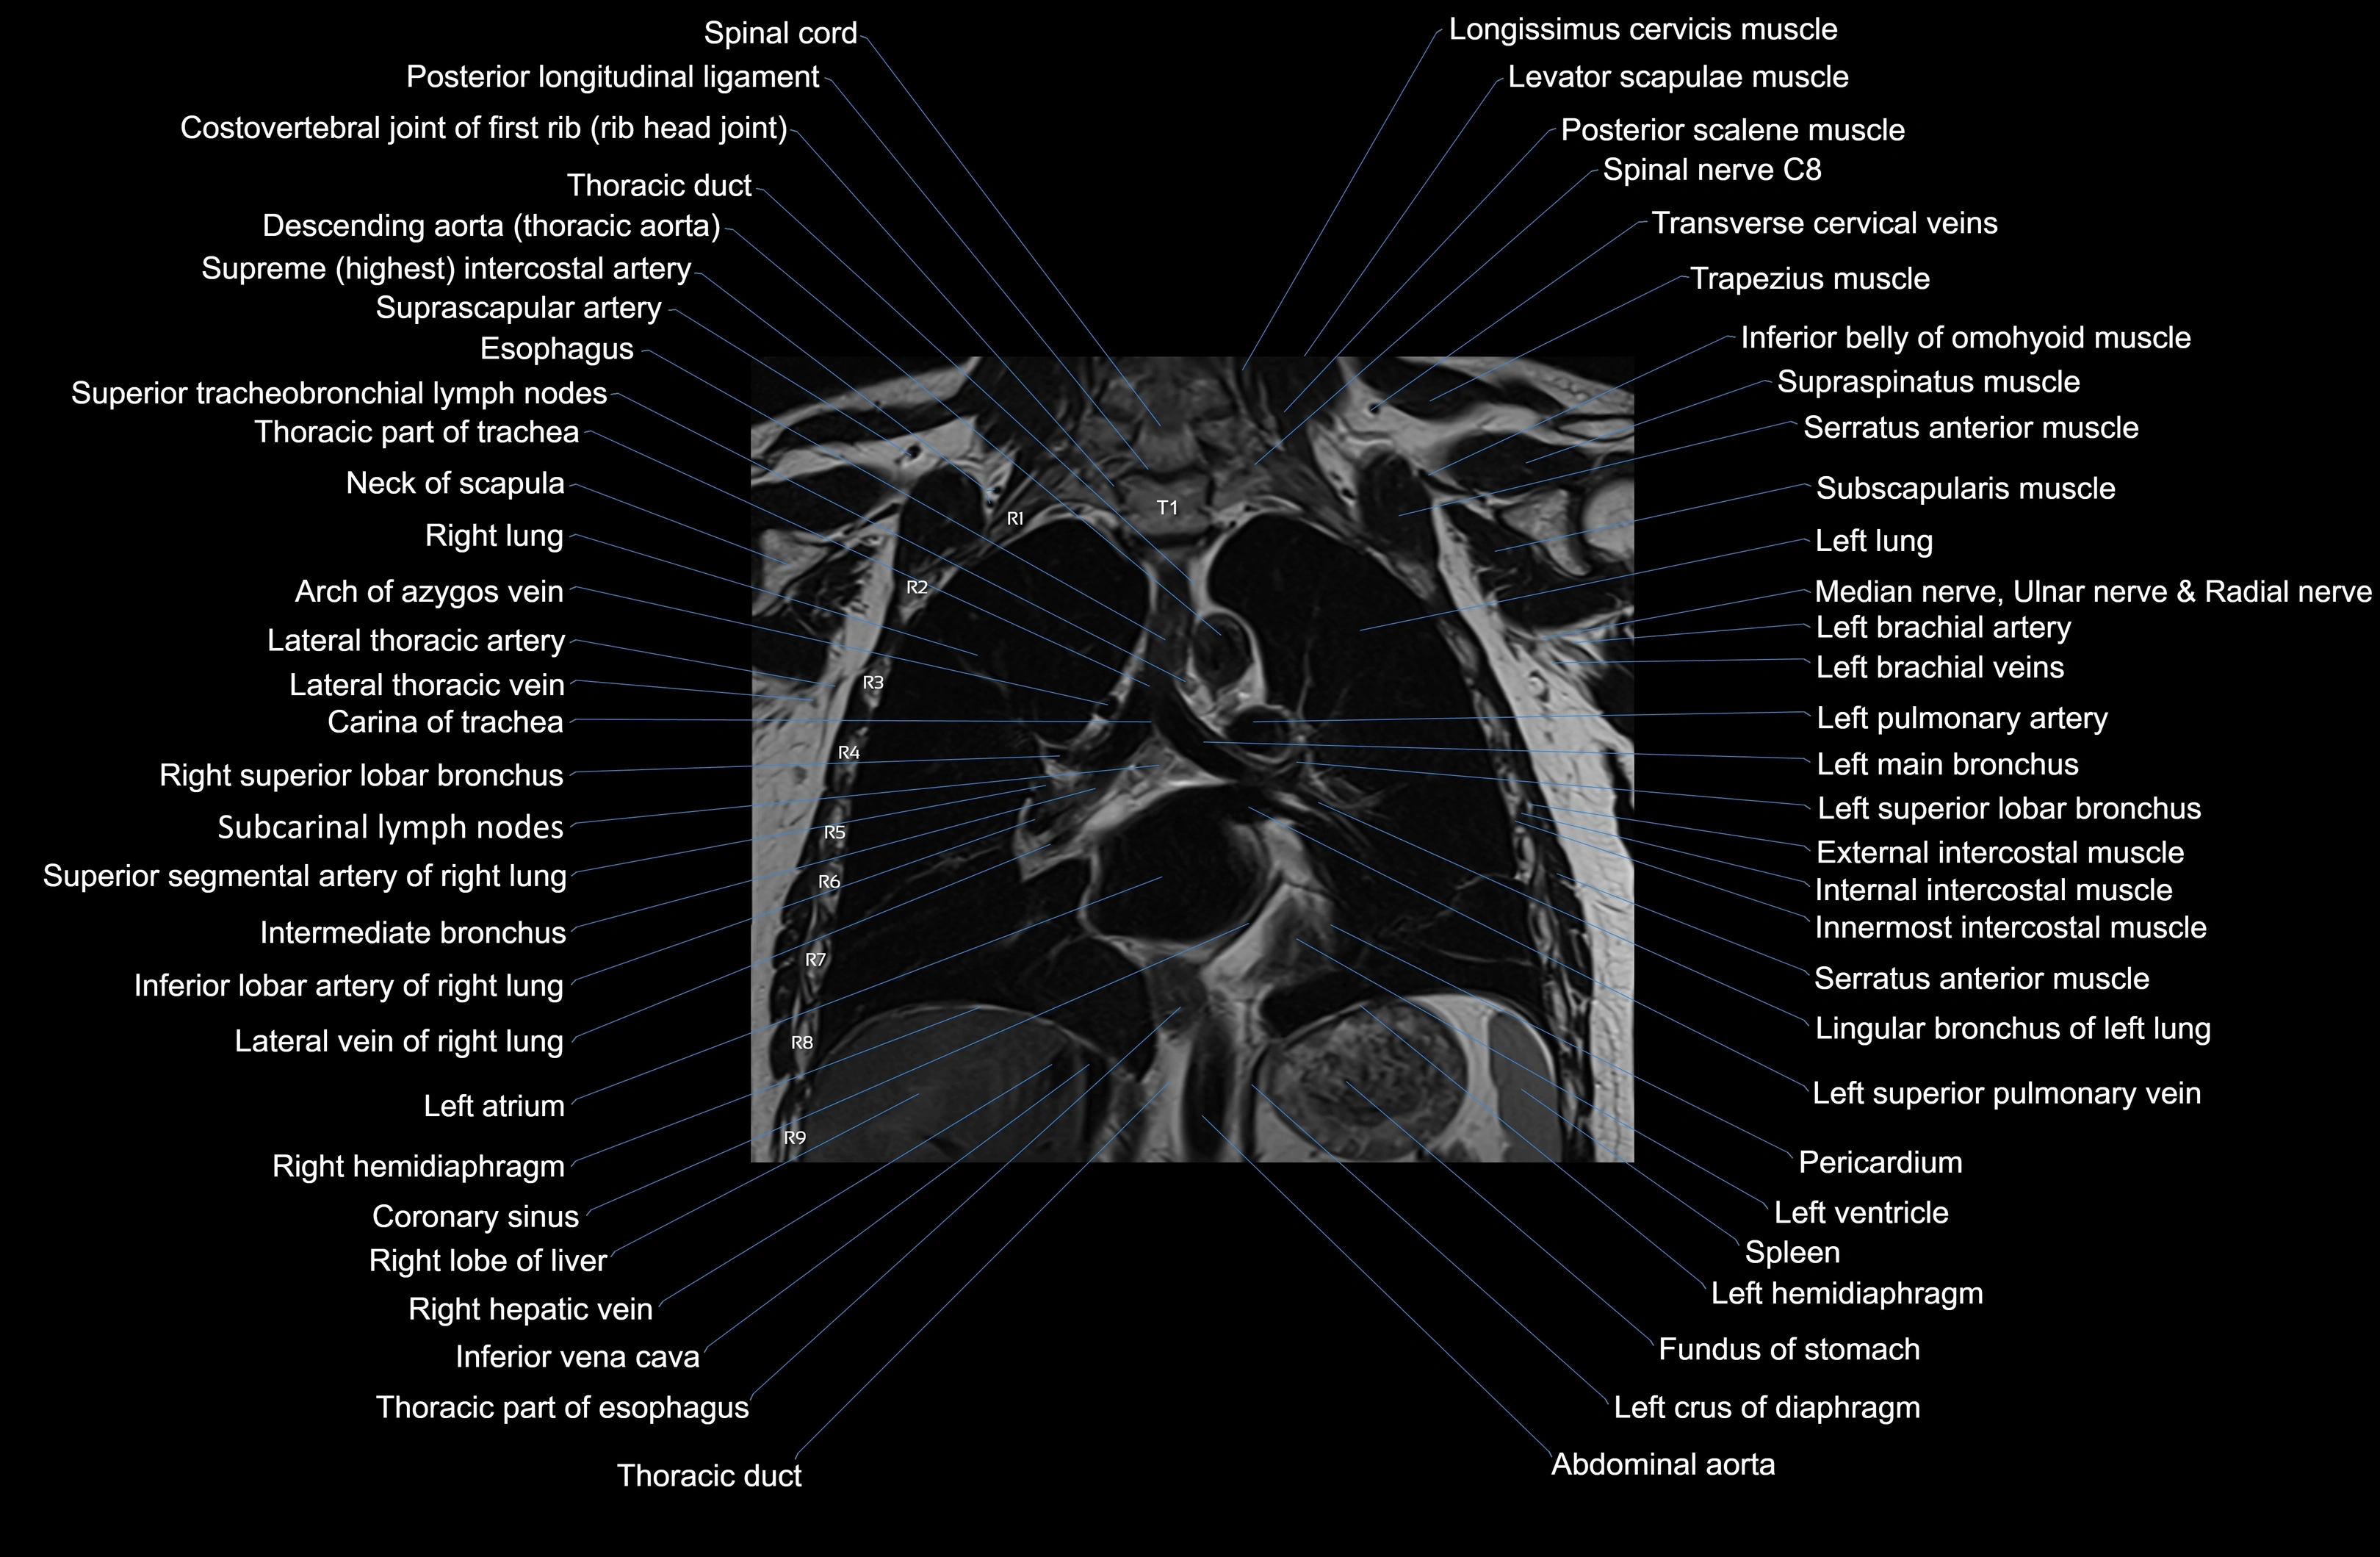

MRI images